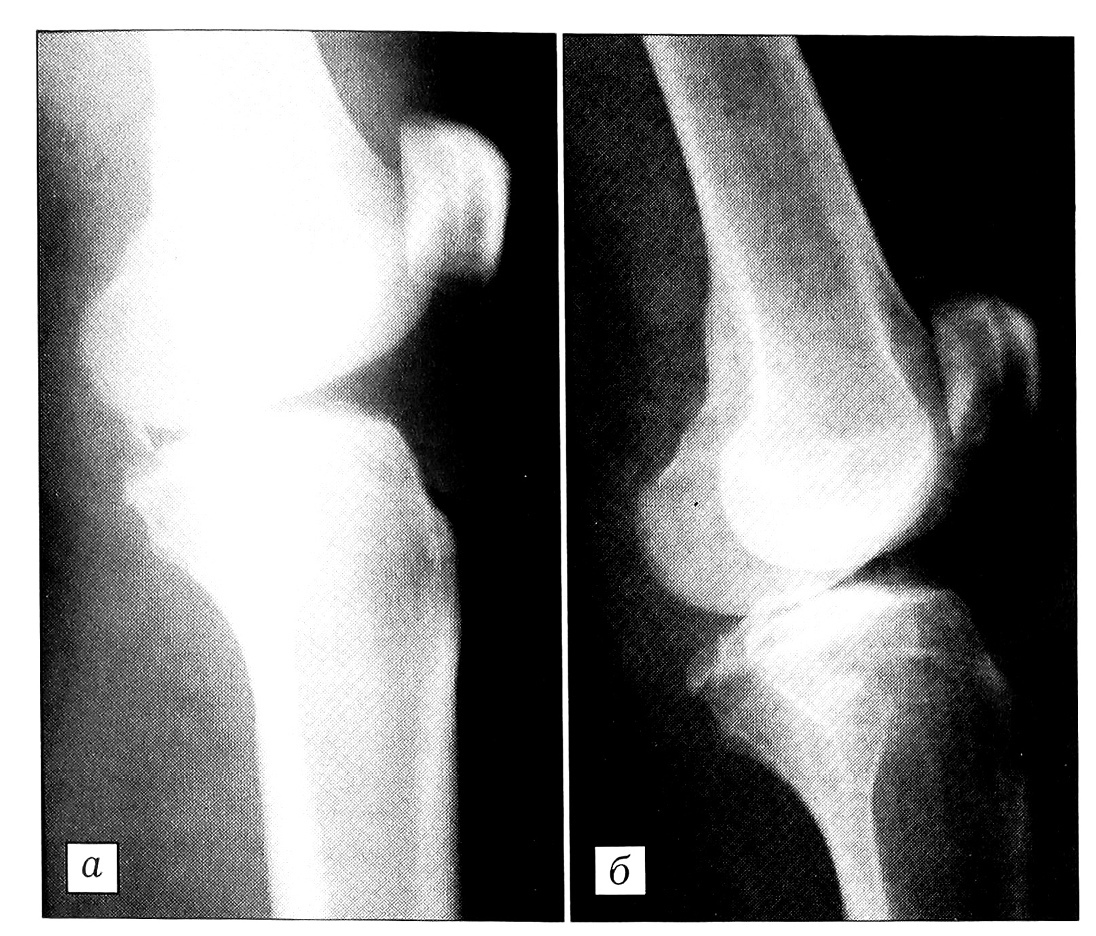

Больной К.,24 лет, не справился с управлением легковым автомобилем, при столкновении с преградой получил сильный удар в переднюю часть коленного сустава. Поступил с выраженным болевым синдромом и значительным отеком в области колена. На рентгенограммах определяется отрывной перелом задневерхнего края большеберцовой кости (рис.3, а). Костный фрагмент больших размеров, смещен от своего ложа более чем на 1 см. При поступлении выполнены пункция коленного сустава, новокаиновая блокада, обработка ссадин. Выявлен положительный симптом «заднего выдвижного ящика». Наложена гипсовая шина. На 6-е сутки после травмы (к этому времени зажили ссадины в области коленного сустава) произведены открытая репозиция и внутренняя фиксация винтом (рис. 3, б). В течение 6 нед после операции продолжалась иммобилизация гипсовой шиной, затем проводились ЛФК и массаж, дозированная нагрузка. Пациент осмотрен через полгода: жалоб нет, сустав стабилен, объем движений полный.

Рис. 3. Рентгенограммы коленного сустава больного К. до (а) и после (б) операции.